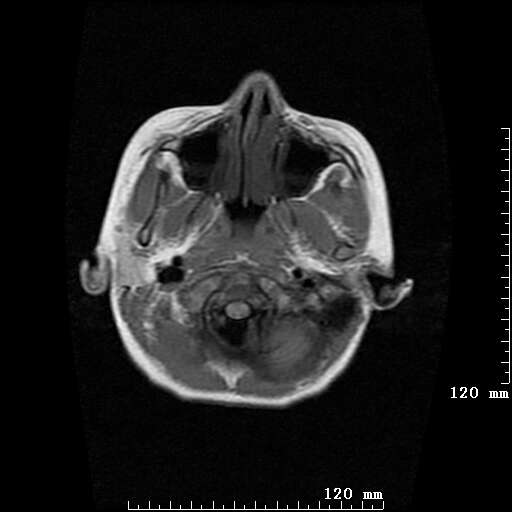

女,7岁,三岁才说话、走路。现智力尚可,走路不稳。临床怀疑大脑发育不全。

考虑 脑白质发育不良

脑折质变薄,双侧侧脑室稍扩张,支持考虑脑折质发育不良

侧脑室周围白质软化症。

考虑胼胝体发育不全,髓鞘形成不良。

支持考虑胼胝体发育不全,髓鞘形成不良。

脑裂畸形伴灰质异位

侧脑室周围白质数量减少,侧脑室不对称性扩大,左侧侧脑室后角呈方形改变,脑沟加深,结合临床考虑脑室周围白质软化症(pvl)。期待结果!

只看出灰质异位

支持脑白质发育不良。